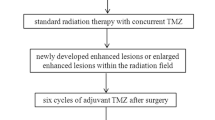

This retrospective study was approved by the Institutional Review Board of our hospital. Because of the retrospective nature of the study, the requirement of informed patient consent was waived. Brain MRI data obtained at our hospital from January 2015 through December 2018 were reviewed to identify postoperative patients who were diagnosed with BT-RADS category 3 lesions during follow-up. Criteria for inclusion in the analysis were: (1) Diagnosis of histologically confirmed HGG after initial surgery, based on World Health Organization criteria; (2) Treatment with CCRT and adjuvant chemotherapy; (3) Increasing enhancing lesions classified as BT-RADS category 3 in comparison with prior imaging data; (4) Conventional MR imaging, DSC PWI, and DWI were performed within 72 h after surgical removal of the tumor; (5) Repeat resection or follow-up information containing the aforementioned imaging studies performed every 3 to 6 months, to determine tumor recurrence after treatment. Patients with incomplete follow-up data, and those whose MR images were of inferior quality that prevented the analyses required for this study were excluded. The BT-RADS category of all cases was independently assessed online (https://btrads.com/publications/) in the light of conventional MR imaging data by a neuroradiologist with more than 10 years of experience.

Diagnostic criteria for recurrence

A total of 91 patients who met the inclusion criteria were identified in the medical records. There were 53 males and 38 females, with a mean age of 48.7 ± 14.2 years (range 9 to 77 years). Of the 91 patients, 51 had tumor recurrences, and 40 did not have a recurrence. Twenty-three (45.1%) of the 51 tumor recurrences and 11 (27.5%) of 40 non-recurrences were confirmed by a second surgery or stereotactic biopsy, and 28 (54.9%) of the 51 tumor recurrences and 29 (72.5%) of 40 non-recurrences were confirmed by standard clinical follow-up. Patient demographic and clinical data by recurrence group are summarized in Table 1. Karnofsky Performance Status (KPS) Scale score and the primary surgery method were significantly different between the tumor recurrence and non-recurrence groups (p = 0.039 and 0.034, respectively). The time interval from CCRT to identification of an abnormal enlarging enhanced lesion was significantly shorter in the non-recurrence group than the recurrence group (6.6 ± 3.4 months vs. 10.5 ± 5.0 months, p < 0.001). Other demographic and clinical data, such as age, sex, tumor grade, isocitrate dehydrogenase (IDH) genotype, and enhancing lesion diameter were not different between the two groups (all, p > 0.05).